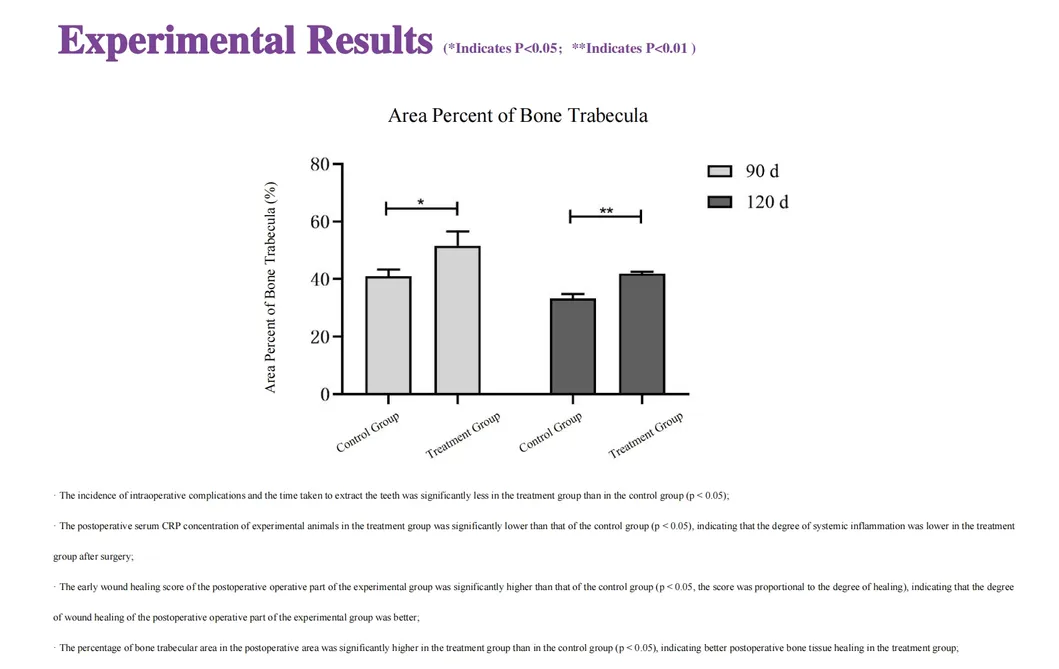

In this groundbreaking study, dogs were selected to assess the effectiveness of the Golden Cudgel-Pneumatic Dental Elevator Kit. Researchers meticulously documented physiological parameters, extraction duration, and socket damage compared to traditional manual devices. The data provides profound insights into the superior performance and efficiency of these advanced dental tools.